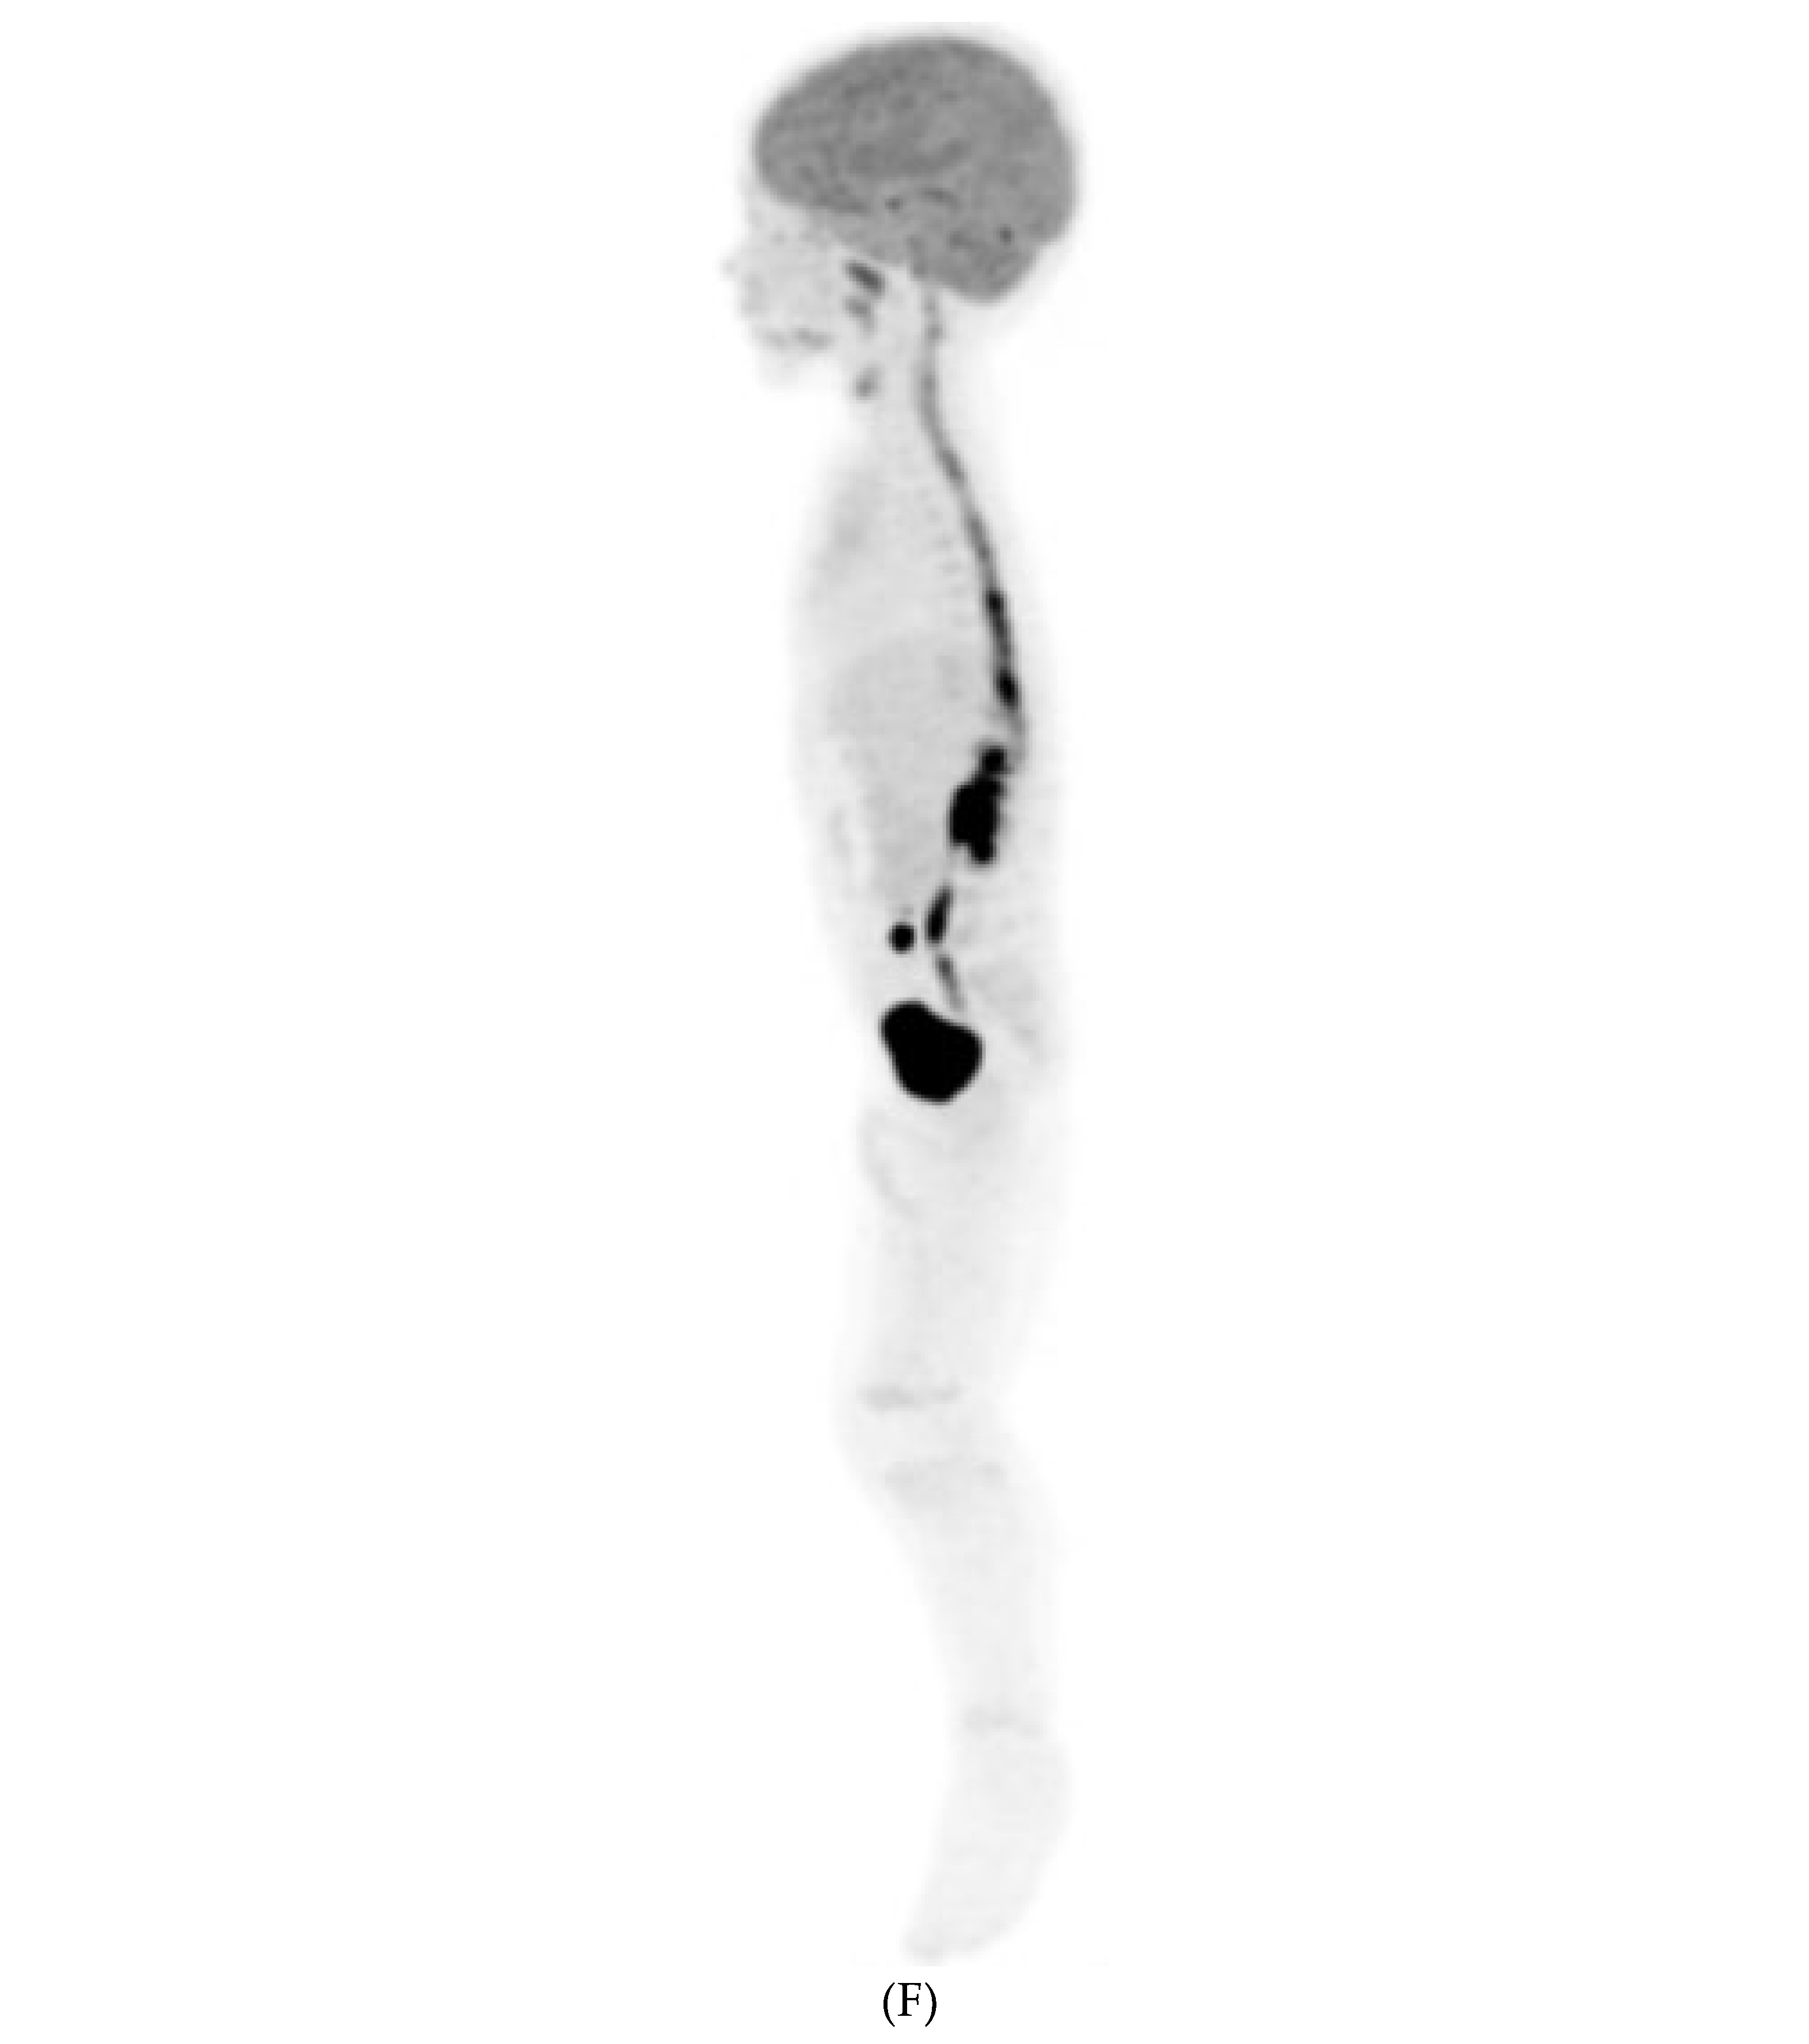

SYSTEMIC MENINGEAL METASTASES (SMM)